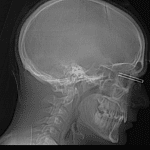

Indication: Left eye foreign body

Findings

- Metallic radiopaque foreign body (large staple) punctures the left globe in two locations with extension into the retrobulbar space. The medial prong of the staple abuts the optic nerve and the lateral prong abuts the lateral rectus muscle

- The globe appears to maintain its normal configuration and the lens appears to be normally located, though evaluation is somewhat limited by metallic streak artifact

- Mild left periorbital soft tissue edema

Diagnosis

- Orbital foreign body

Metallic radiopaque foreign body (large staple) punctures the left globe in two locations with extension into the retrobulbar space. The medial prong of the staple abuts the optic nerve, which may be damaged, and the lateral prong abuts the lateral rectus muscle. No large retrobulbar hematoma or proptosis.

The globe appears to maintain its normal configuration and the lens appears to be normally located, though evaluation is somewhat limited by metallic streak artifact.